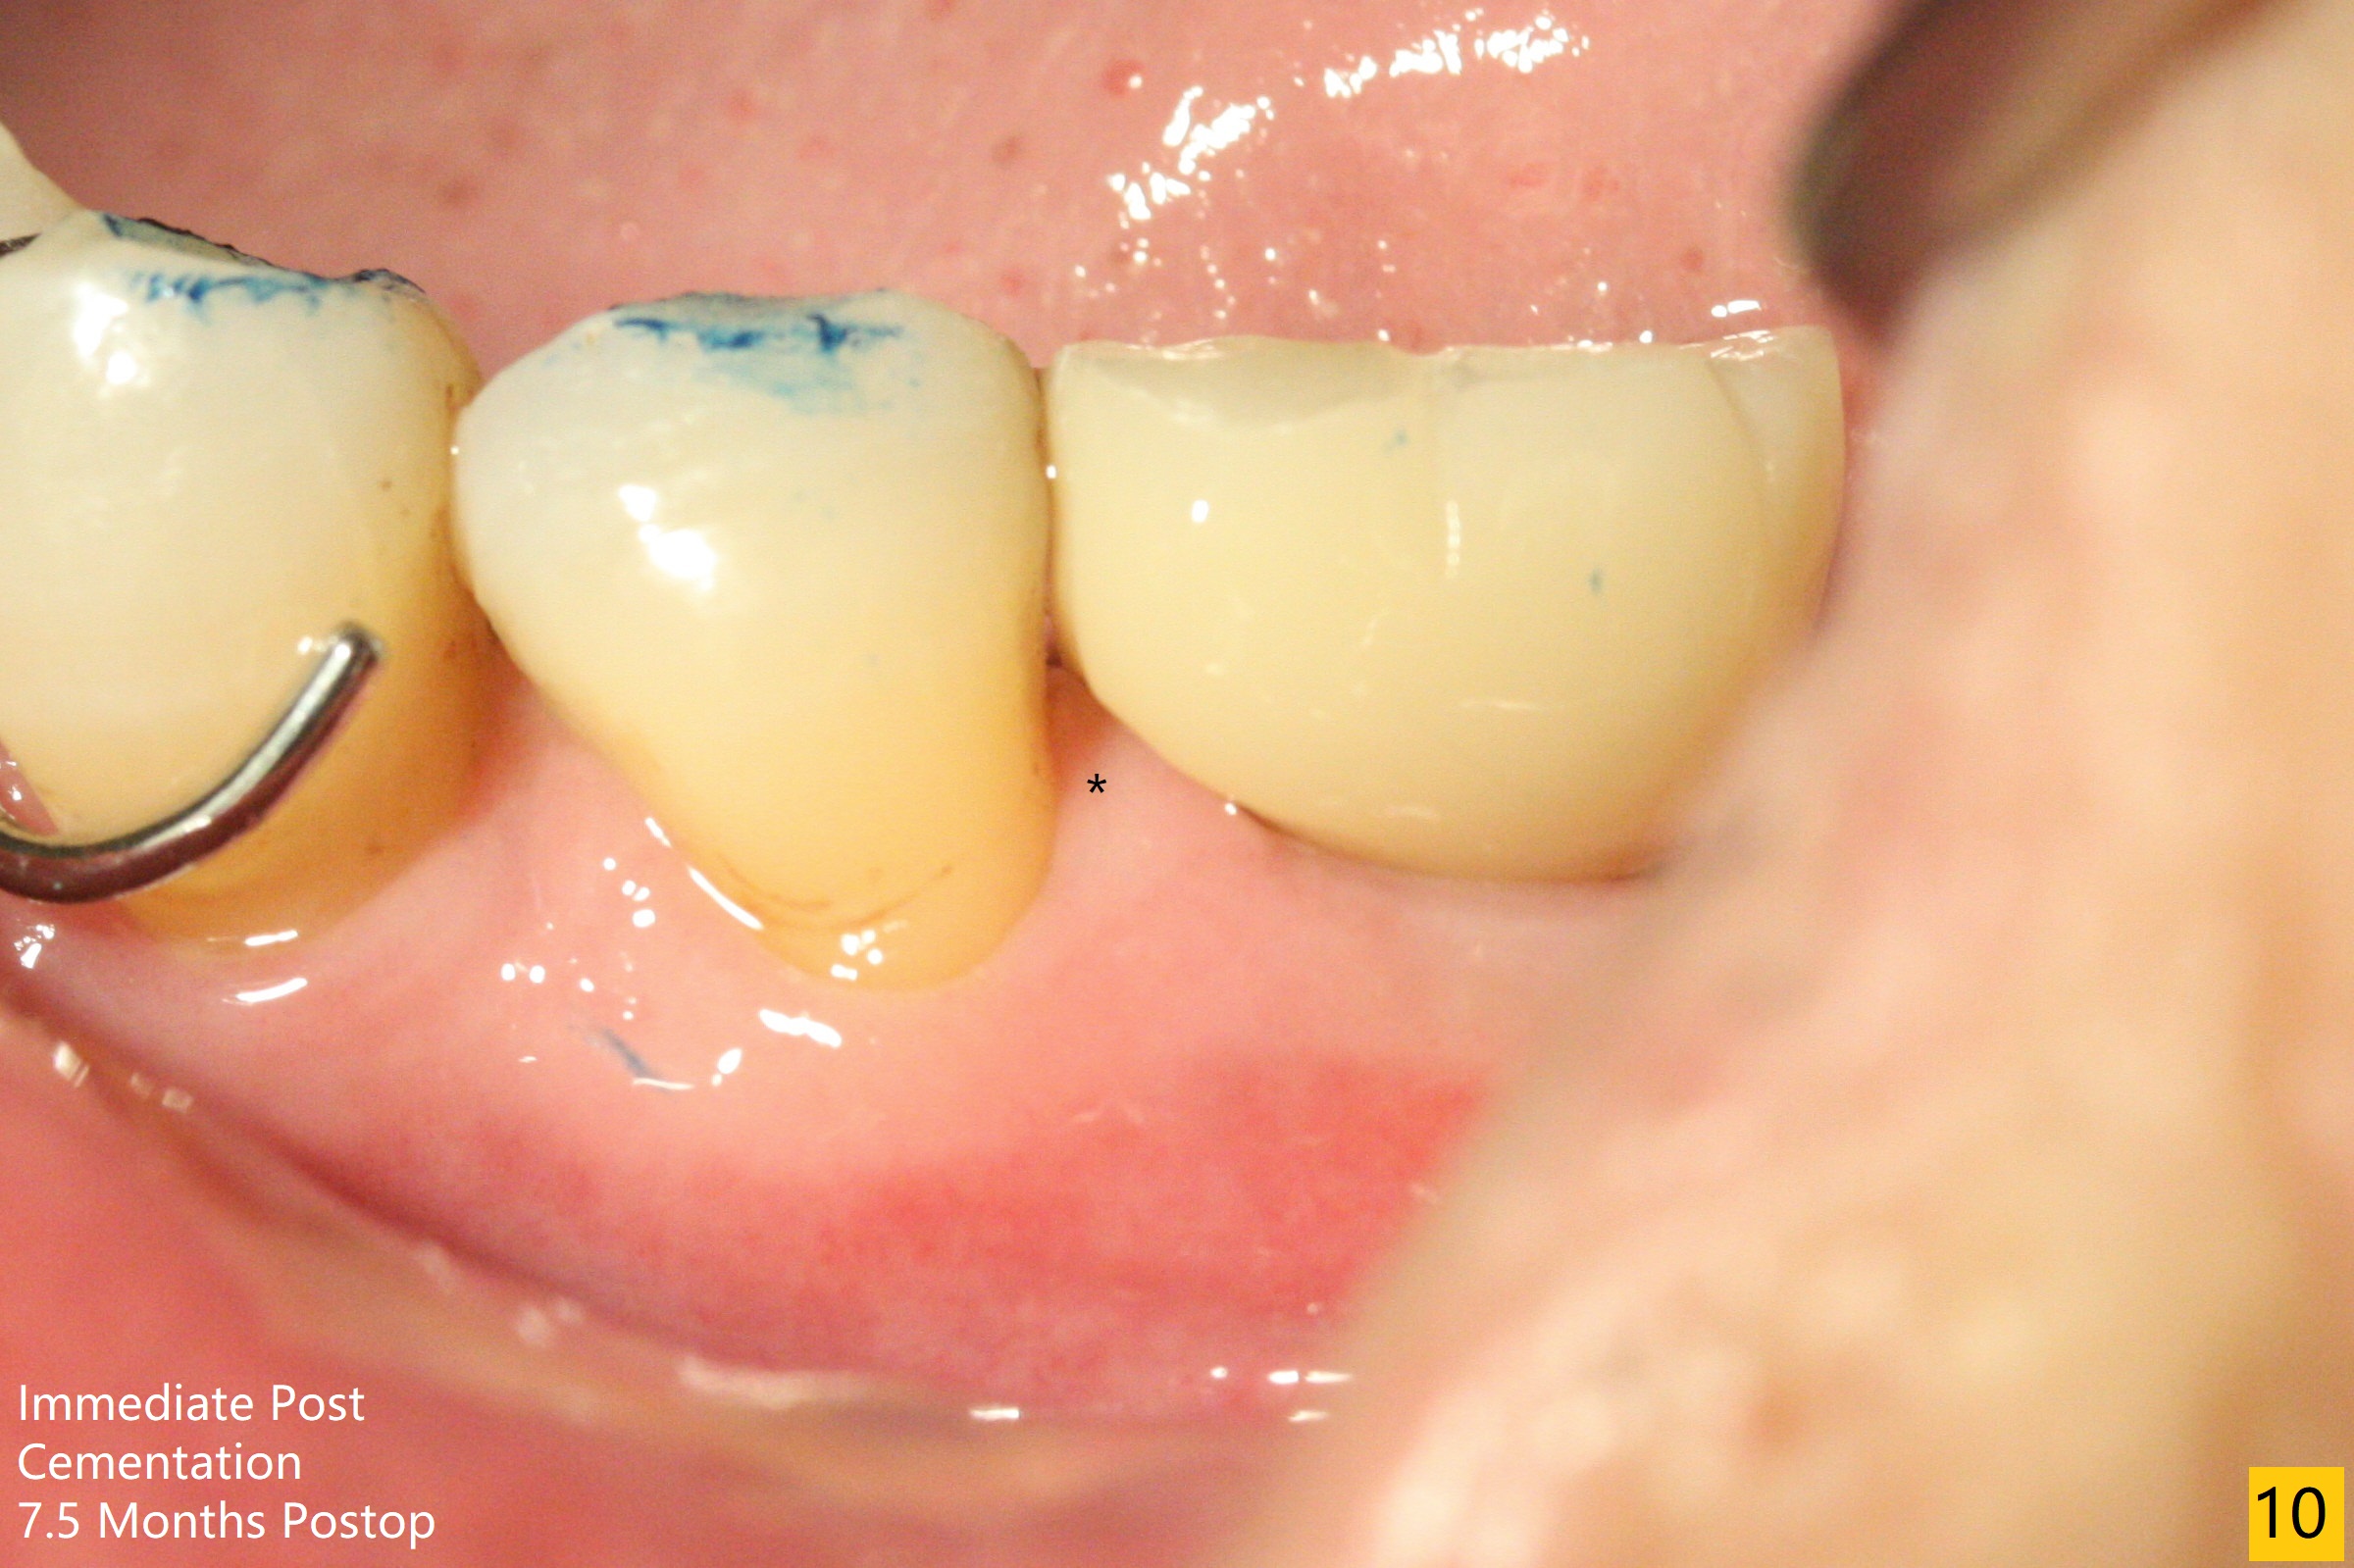

A 68-year-old man returns for extraction of the tooth #19 with distal root periodontal-endodontic lesion (Fig.1 *). After discussion, he agrees immediate implant. A 4.5x11.5 mm implant will be placed in the mesial socket (Fig.2 (red line: superior border of Inferior Alveolar Canal)); the plateau level with the septal crest (<). Osteotomy is initiated in the lingual slope of the mesial socket; the depth is controlled with stopper (Fig.3 S). The implant is placed at the level as expected (Fig.4 <) with insertion torque ~30 Ncm; after placement of 5.7x4(3) mm abutment and Osteogen plug (P) in the apical half of the distal socket, bone graft (G) is placed in the remaining socket gaps, mainly distal and buccal. An immediate provisional is fabricated to keep the graft in place (Fig.5 T). The graft may be lost if the gingival margin recedes in healing. Periodontal dressing is applied for additional security (Fig.6). There is no postop paresthesia. The upper border of the Inferior Alveolar Canal in Fig.3,4 seems to be high. In fact it may be a branch of the Inferior Alveolar Canal (Fig.7 yellow line, as compared to Fig.4). With all of measures taken (including periodontal dressing), the distal bone graft (Fig.8 *) is ~ 2 mm coronal to the crestal bone (red line) 6 months postop. The temporary crown is perforated. The gingival cuff is erythematous. A 6.8x5 mm healing abutment is installed. When the patient returns for impression, a 4.5x5.5(3) mm abutment is fully seated (Fig.9 <). The distal height increases by 4 mm because of immediate implant (support). The mesial papilla remains normal in height and shape immediate post cementation (Fig.10), as related to the mesial socket implant placement without mesial crestal bone loss. The mesial and distal crestal height is maintained 13 months post cementation (Fig.11, weight lifter).